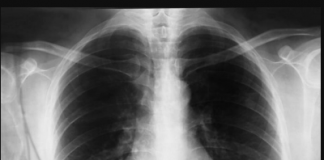

PULMOLOG MIODRAG OTKRIO KOJI JE NAJBOLJI LIJEK ZA UPALU PLUĆA: Ove...

Značajni zdravstveni problemi poput upale pluća i kroničnog kašlja mogu ozbiljno utjecati na kvalitetu života pojedinca. Nevolja koja proizlazi iz simptoma uključujući bol u...